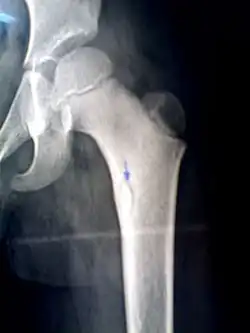

A sequestrum (plural: sequestra) is a piece of dead bone[1] that has become separated during the process of necrosis from normal or sound bone.

It is a complication (sequela) of osteomyelitis. The pathological process is as follows:

- infection in the bone leads to an increase in intramedullary pressure due to inflammatory exudates

- the periosteum becomes stripped from the ostium, leading to vascular thrombosis

- bone necrosis follows due to lack of blood supply

- sequestra are formed

The sequestra are surrounded by sclerotic bone which is relatively avascular (without a blood supply). Within the bone itself, the haversian canals become blocked with scar tissue, and the bone becomes surrounded by thickened periosteum.